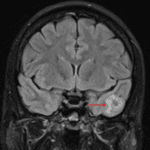

CT

- Ill-defined mixed hypoattenuating and hyperattenuating lesion in the inferior left temporal lobe

MRI

- Mixed cystic and solid mass in the inferior left temporal lobe measuring 1.6 x 1.5 x 1.3 cm with mild surrounding vasogenic edema

- The solid components diffusely enhance

- No corresponding restricted diffusion

- No substantial mass effect

Ganglioglioma